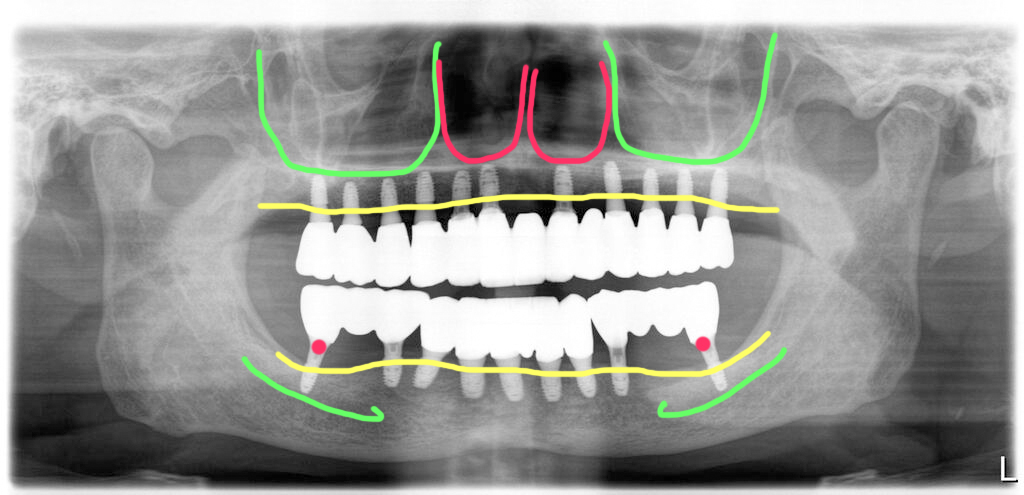

오늘 설명해 드릴 사례는 60대 남성 환자로 완전무치악 상태였습니다. 임플란트 치료로 치아를 재건하고자 오셨습니다.

치아가 완전히 없는 상태에서 꽤 오랜 시간이 지나서 치조골 높이가 많이 낮아져 있습니다. 위턱 아래턱 모두 뼈가 있지만 높이가 충분하지는 않았습니다. 무리하게 긴 임플란트 식립을 하지 않고 이용할 수 있는 뼈 내서 길이를 정해 식립하기로 결정했습니다.

완전 무치악 상태

완전 무치악 상태였기 때문에 뼈는 부족했지만 염증은 없어서 수술은 깔끔하게 진행되었습니다.

다만 아래 어금니 부위에 신경관이 너무 가까워 해당 부위는 신경관을 피해서 식립을 했습니다.

보통 이런 경우 앞쪽에만 식립해서 어금니 부분을 캔틸레버로 만들기도 하지만 제일 마지막 치아가 있으면 훨씬 역학적으로 유리하므로 어렵게 식립을 시도했습니다.